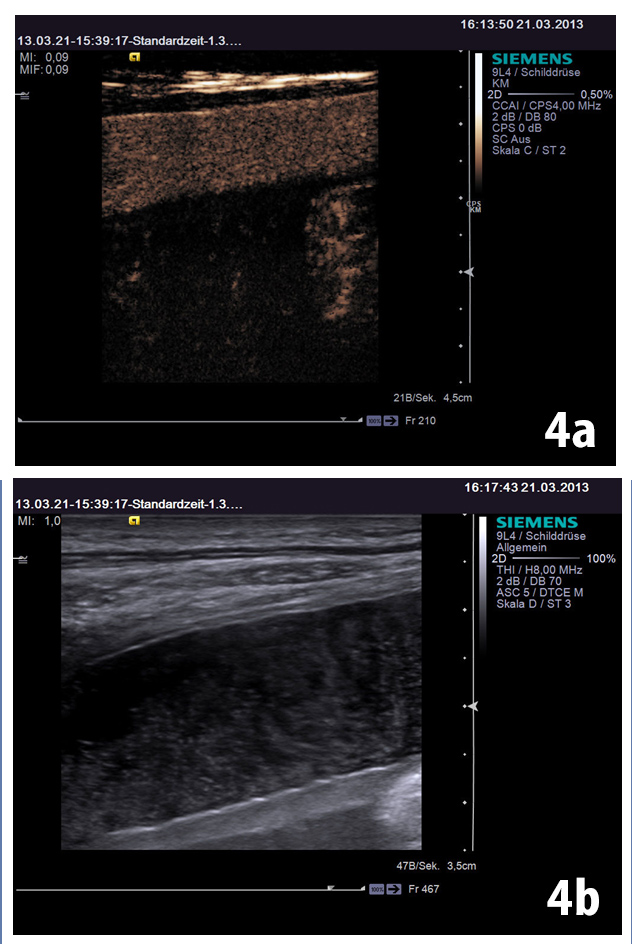

Contrast enhanced ultrasound (CEUS) with high frequency probe showed in the near field that the lesion was extraperitoneally located (Fig 4).

Figure 4: Contrast enhanced ultrasound with high frequency probe showed the lesion was extraperitoneal (a) [see also Figure 1 and 2b]. Artefacts may be encoun-tered (b) [(1-3)].